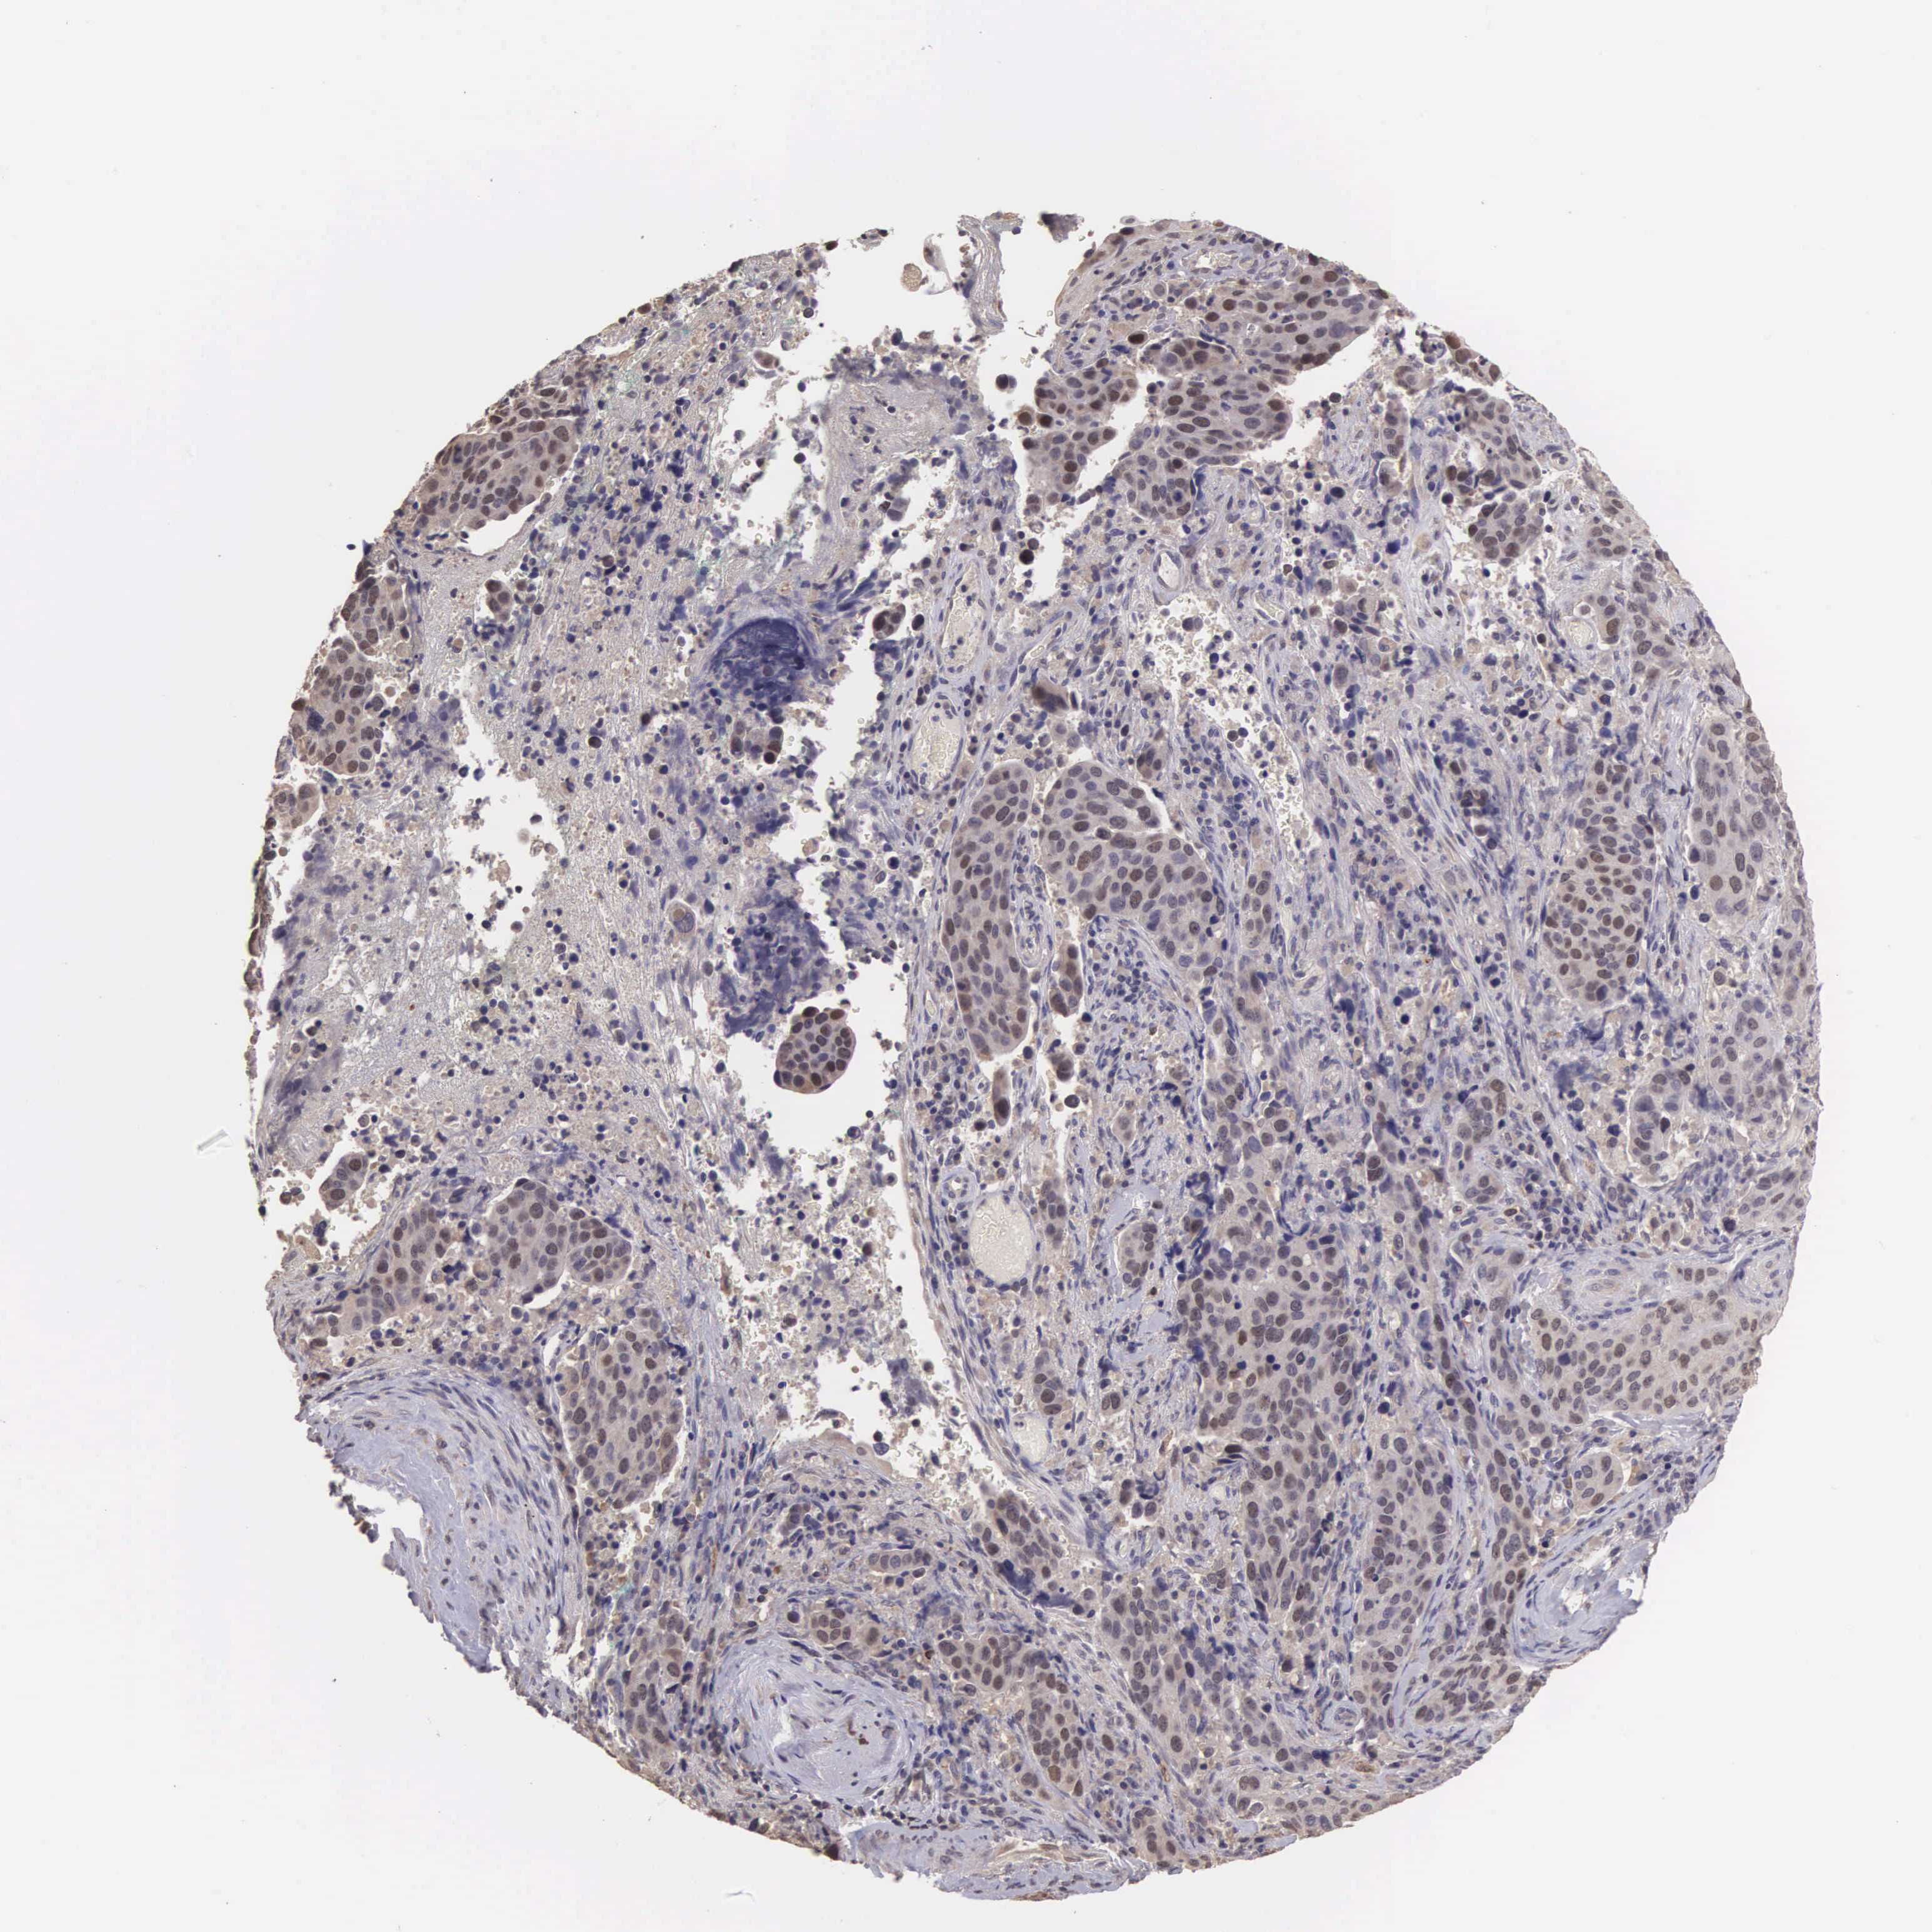

CERVICAL CANCER - Protein expressioni

A mouse-over function shows sample information and annotation data. Click on an image to view it in a full screen mode. Samples can be filtered based on level of antibody staining by selecting one or several of the following categories: high, medium, low and not detected. The assay and annotation is described here.

Note that samples used for immunohistochemistry by the Human Protein Atlas do not correspond to samples in the TCGA dataset.

Antibody stainingi

Antibody staining in the annotated cell types in the current human tissue is reported as not detected, low, medium, or high, based on conventional immunohistochemistry profiling in selected tissues. This score is based on the combination of the staining intensity and fraction of stained cells.

Each image is clickable and will lead to virtual microscopy that enables deeper exploration of all samples and also displays staining intensity scores, fraction scores and subcellular localization as well as patient and tissue information for each sample.

Antibody HPA000614

Antibody CAB009459

Staining

High

Medium

Low

Not detected

Intensity

Strong

Moderate

Weak

Negative

Quantity

>75%

75%-25%

<25%

None

Location

Nuclear

Cytoplasmic/membranous

Cytoplasmic/membranous,nuclear

Adenocarcinoma, NOS

Squamous cell carcinoma, NOS